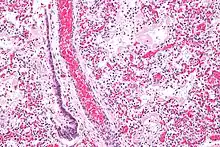

В основе ОРДС лежит диффузное воспаление лёгких. В этом процессе выделяют 3 фазы: экссудативная, пролиферативная и фибротическая[8].

В экссудативную фазу в ответ на воспаление выделяются цитокины и другие провоспалительные вещества, которые активируют альвеолярные макрофаги и циркулирующие нейтрофилы. В свою очередь, активированные нейтрофилы прикрепляются к эндотелию лёгочных капилляров и высвобождают содержимое своих цитоплазматических гранул (протеазы и токсические метаболиты кислорода)[10]. Это приводит к повреждению эндотелия капилляров и эпителия альвеол, нарушая альвеолярно-капиллярный барьер. В результате экссудат проникает в лёгочную паренхиму и альвеолярное воздушное пространство. Нарушается газообмен и возникает гипоксия[11]. Также возможно повреждение альвеолоцитов II типа, которые отвечают за образование сурфактанта. При этом происходит спадение альвеол, снижение растяжимости лёгких и внутрилёгочное шунтирование. Кроме того, развивается лёгочная гипертензия в результате внутрисосудистой обструкции тромбами, спазма лёгочных сосудов из-за гипоксии и действия некоторых воспалительных медиаторов (тромбоксан, лейкотриены и эндотелин)[12].

В пролиферативную фазу у большинства пациентов происходит восстановление лёгких: удаляется экссудат, нейтрофильная инфильтрация сменяется лимфоцитарной. Пролиферируют альвеолоциты II типа, которые образуют новый сурфактант и дифференцируются в альвеолоциты I типа. Но несмотря на такие улучшения, у многих больных сохраняется одышка, тахипноэ, гипоксемия[8]. У некоторых пациентов процесс переходит в фибротическую фазу. Накопленный в лёгких фибрин подвергается ремоделированию и может вызывать фиброз[13].